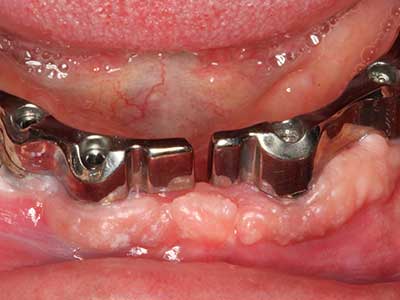

Purely orthodontic indications include orthognathic surgery, genioplasty (Fig. 27-30) and orbital decompression in patients with advanced endocrine orbitopathy as a result of Basedow’s disease (Ponto, Zwiener et al. 2014). Piezo devices are also used in maxillofacial surgery and to remove tumours at the base of the skull in various hospitals.